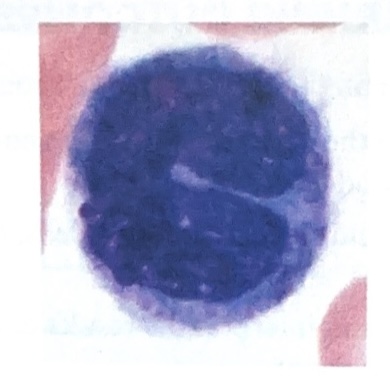

Lymphocytes

Slightly larger that RBC’s

Thin rim of nearly clear cytoplasm

Nearly round nucleus appears to fill most of cell in smaller lymphocytes

Larger lymphocytes hard to distinguish from monocytes